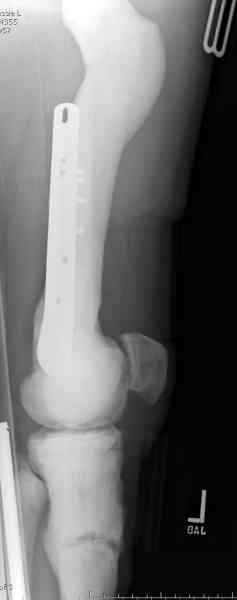

После неудачной попытки скелетного вытяжения в первом мед.учреждении, после осмотра снимков и изучения истории, поставили диагноз “Остеопетроз” или мраморная болезнь, редкая наследственная костная паталогия, где имеется нарушение формации остеокластов.

Конечно, было бы идеальным применение интрамедуллярного остеосинтеза, но учитывая прежний собственный опыт (лечил перелом бедра) и

публикации, предупреждающие о трудностях при обработке кости (иногда из-за неподготовленности инструментария результатом была неадекватная фиксация перелома, или перенос операции из-за фактора усталости оперирующего персонала), решили применить пластину (и в этом же случае был выбран Synthes plate, так что представитель за два дня

зароботал... на десерт тоже).

Заказаны были дополнительные различные дрели, и на следующий день, усиленной бригадой, больного прооперировали, потратив на каждое отверстие около 25-35 минут, хотя сверлили с охлаждением по нарастающей по диаметру сверл и с их заменой каждые 2 мм сверления.

Теперь стоит задача со сращением перелома, из-за отсутствия литературных данных по применению костных стимуляторов при остеопетрозе, и не зная как поведет в этой среде Grafton, все таки надеюсь, что даст толчок к стимуляцию, решил применить пастообразную деминерализованную костную матрицу, расположив спереди между отломками.